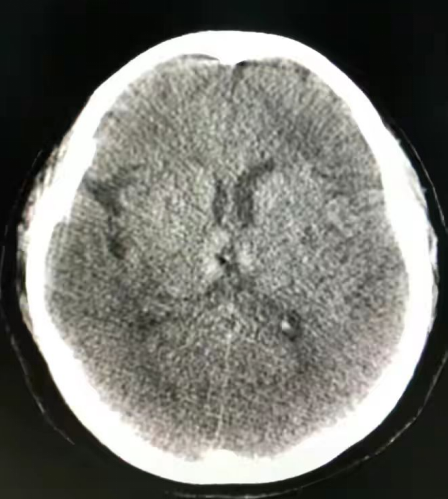

在神经介入的临床运用上,类CT能够清晰显示颅内影像,对于急性脑梗要进行介入治疗的,可以省去去CT检查室的时间,直接进入导管室进行类CT检查,手术结束后也可以直接做对比,为病人争取了宝贵时间。而行颅内支架或动脉瘤栓塞、动静脉瘘的栓塞,可以清楚显示颅内是否有出血情况,也省去去CT检查室的时间。